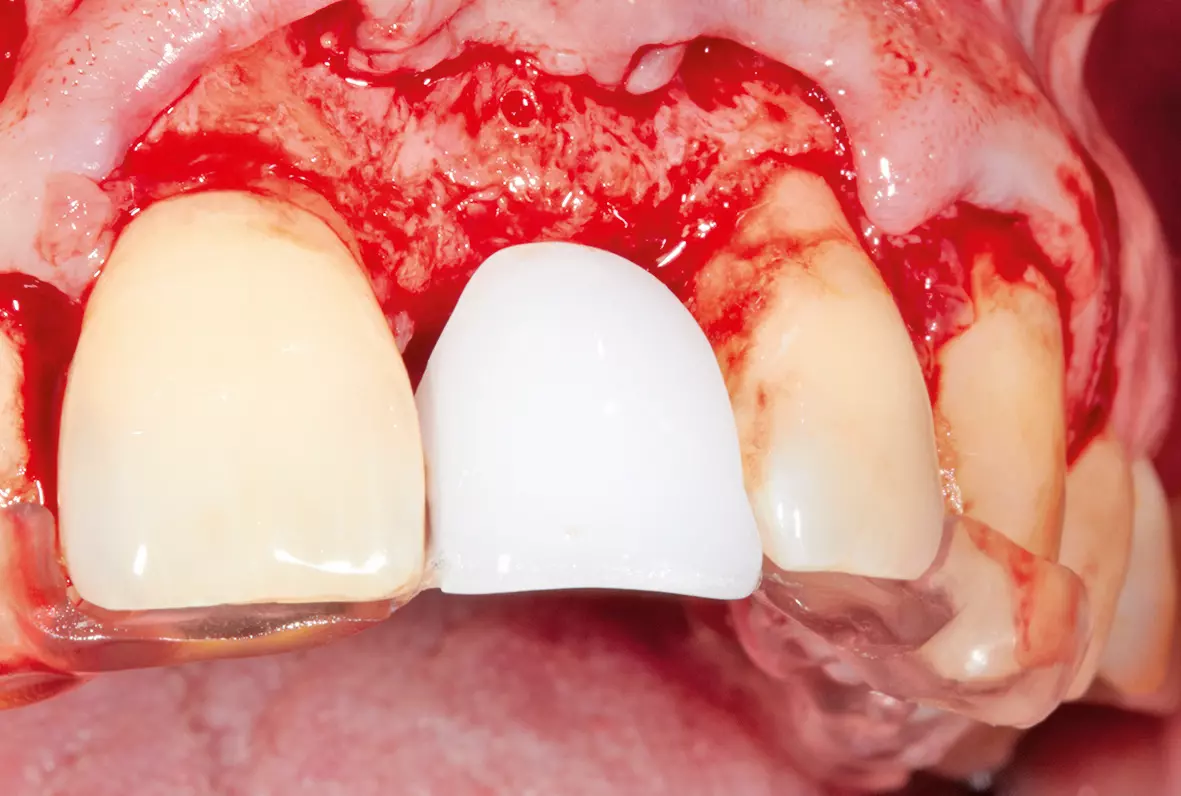

Nach der Heilungsphase war für einen Aufbau der vestibulären Lamelle ein Knochentransplantat aus dem Kieferwinkel erforderlich. Dies sorgte für eine gute und gleichmäßige Ausformung des Vestibulums und es bestand die Möglichkeit, das Implantat an die gleiche Stelle wie die Zahnwurzel zu setzen (Abb. 5 und 6).

Nach einer Einheilphase von drei Monaten konnte implantiert werden. Es sollte eine okklusal verschraubte Krone verwendet werden. Die Entscheidung des Implantatsystems fiel auf ein ELEMENT Implantat von Thommen Medical, da es über einen sehr kleinen Schraubenkanal verfügt und damit eine gute prothetische Versorgung – gerade im Frontzahnbereich – ermöglicht. Hier hat man es häufig mit Problemen der Einschubrichtung des Implantates zu tun und ein kleiner Schraubendurchmesser schafft Platz, um eine Verschraubung möglich zu machen. Für die Implantation erfolgte in Lokalanästhesie eine krestale, leicht lingual versetzte Schnittführung unter Erhaltung eines einige Millimeter breiten Streifens befestigter Mukosa. Das Implantat wurde in korrekter Position ca. 3-4 mm oberhalb der Schmelz-Zement-Grenze sowie ca. 2 mm oral von der Verbindungslinie der benachbarten Wurzeloberflächen und mit einer Implantatachse palatinal von der geplanten Schneidekante gesetzt (Abb. 7 und 8). Danach wurde ein steriler Abformpfosten für eine offene Abformung aufgeschraubt. Zur Anfertigung des Index wurde Triad Gel (Triad Gel Clear Colorless, Dentsply International, York, PA, USA) benutzt. Dazu wurde das Material in eine sterile 2-ml-Einmal-Spritze gefüllt und auf den Abformpfosten und beide Nachbarzähne aufgetragen. Die Aushärtung erfolgte mit einer in eine sterile Folie eingepackten Polymerisationslampe.

Durch den Aufbau des räumlich korrekten Knochenvolumens konnte bei der Implantatplatzierung die ursprüngliche Situation wiederhergestellt werden. Als „Wax-up“ diente der extrahierte Zahn (Abb. 11). So konnte jetzt entweder gleich die definitive Krone oder eine provisorische Krone hergestellt werden. Wir entschieden uns für die Herstellung einer provisorischen Krone, um die Reaktion der Gingiva auf die Implantatkrone zu beobachten und gegebenenfalls noch darauf reagieren zu können (Abb. 12 bis 14).

Die alte Situation wurde mithilfe eines Vorwalls erhalten. Hiermit konnte eine provisorische Krone hergestellt werden. Durch die ausbrennbare VARIOeco Kunststoffkappe für Titanbasis des Thommen Medical Implantatsystems war es nach einer Kontrolle der Einschraubrichtung des Implantats möglich, den ursprünglichen Zahn in Wachs nachzubilden. Da die räumliche Dimension definiert war, konnte die provisorische Krone in Presskeramik umgesetzt werden (Abb. 15 und 16).